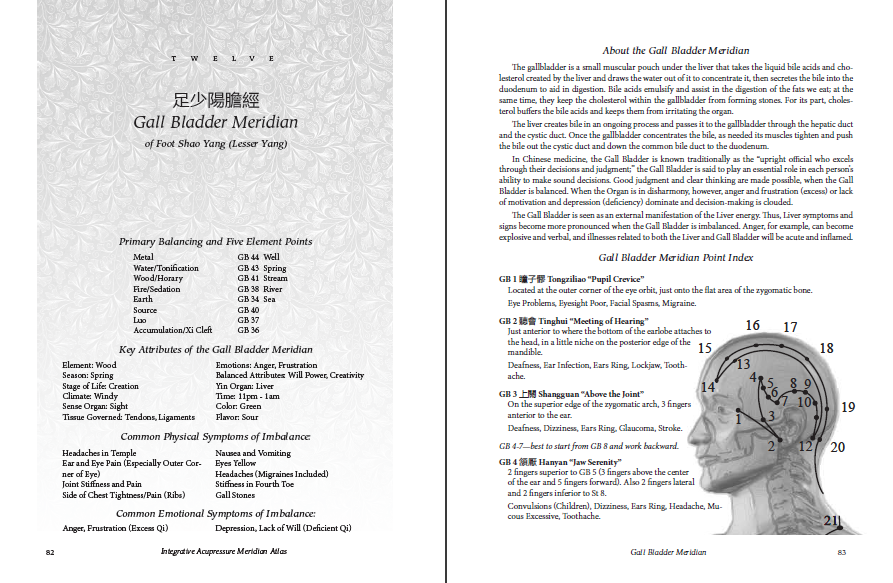

Why use an acupressure atlas instead of an acupuncture atlas? Bodywork is different from needling. Acupuncture charts are designed for finding the precise location of the acupuncture points, but an acupuncturist doesn’t need to know the exact location of the meridian itself. Because of this, most acupuncture charts show a simplified version of the path of the meridian.

In acupressure, along with working on points we typically “trace” (massage) along the course of a meridian to clear blockages and promote Qi flow. The Acupressure Atlas charts include the actual course of each meridian, including the branch pathways not included in most acupuncture charts.

Similarly, an acupuncturist has no need to locate the six extraordinary meridians that have no points of their own, but in acupressure it can be very helpful to trace these meridians.

In addition, the normal method of measurement in acupuncture is the cun, a measurement based on the width of the thumb at the first joint. This makes sense if you are measuring where to put a needle. But in acupressure, we are measuring from one finger placement to another. Measuring the distance between points in this way removes your fingers from the points, which doesn’t make sense. For this reason, point locations are shown in finger distances, where you have your fingertips on each point.